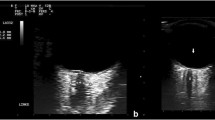

After reviewing in detail each of the studies included, the reported technical settings were identical in terms of probe frequency (a 7.5 MHz linear probe), with the exception of three studies that mentioned a range of frequencies rather than any single one [17,18,19].

Regarding the position of the ONSD measurement, all studies reported an initial measurement 3 mm behind the globe, retina, or papilla, whereas one study measured 2.8 mm behind the globe, and another in a range of 3–4 mm [20, 21]. Probe orientation for ONSD ultrasound was mentioned in four studies (Table 1). In three studies, the orientation was axial only [1, 21, 22]. In one, orientation was both axial and sagittal [23]. In the previous study and one other, a description of patient positioning during the ultrasound study (head of bed at 30°) was made [23, 24].

Regarding the method of estimating the final ONSD measurement, ten studies reported how they obtained the final value in mm (Table 1). Some considered an average of four values (one axial and one sagittal measurement for each eye) [23, 25] while some used an average of three values [19, 26, 27] or an average of two values [17, 20, 21, 28, 29]. The remaining included studies did not mention any details regarding the methods for obtaining the final ONSD measurement [18, 22, 24, 30,31,32].

With respect to the sonographic techniques for ONSD evaluation and assessment of other similar parameters described in the analyzed studies, the information extracted was generally highly variable in terms of the probe’s plane of orientation/insonation [25, 41], patient positioning [23, 24], anatomical landmarks for ONSD measurement [19], and final ONSD measurement calculation methods (Table 1). It is worth mentioning that there were three additional proposed methods apart from ONSD for nICP estimation: ODE [18], ONSD/ETD ratio [19], and a formula-based method leveraging calculated ONSD values (Table 1) [25]. Some of these methods demonstrated better correlation with ICPi and even greater sensitivity and specificity than ONSD alone [18, 19]. Such methods may represent an attempt to individualize ONSD measurements by taking into account eyeball size and its relation to ONSD for each patient [19]; however, there are also recently published data that contrarily report no correlation between global size and ONSD in a healthy Latin American population, creating possible uncertainties regarding the usefulness of these techniques for nICP assessment [42]. On the other hand, these methods may constitute a sonographic assessment of optic disk changes, which may be detected earlier than changes in routine fundoscopy, specifically papilledema [18, 43]. Thus, specifically, the formula-based method proposed by Robba et al. may have a great potential for nICP estimation, although it must be validated in further studies before any considerations regarding its efficacy and accuracy for this purpose can be made (Table 1) [25]. Given the huge differences in the described methods for ONSD ultrasound estimation among all studies, there is undoubtedly a need for establishment of a formal protocol that considers the aforementioned parameters, includes details that may not be as obvious (such as the position of the patient’s gaze during measurement), and can be applied across different regions of the world. Currently, there are emerging data that could represent important starting points, such as anatomical landmark identification and a quality checklist [44, 45].